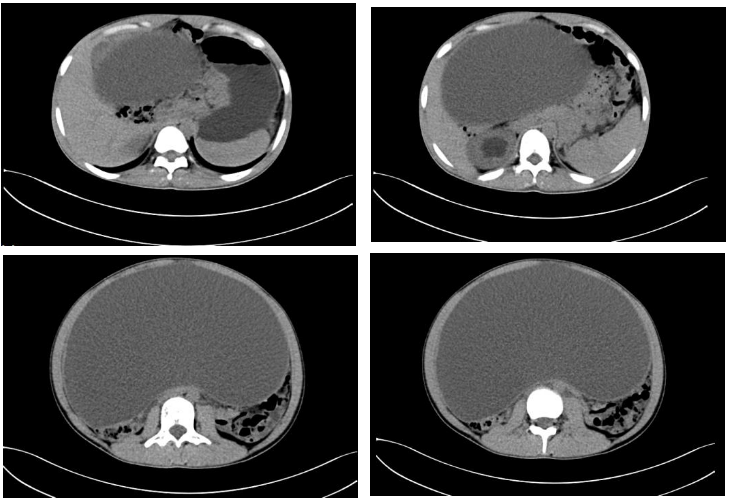

卵巢癌,等你分析丨读片专栏1171期_检查

图片尺寸976x720